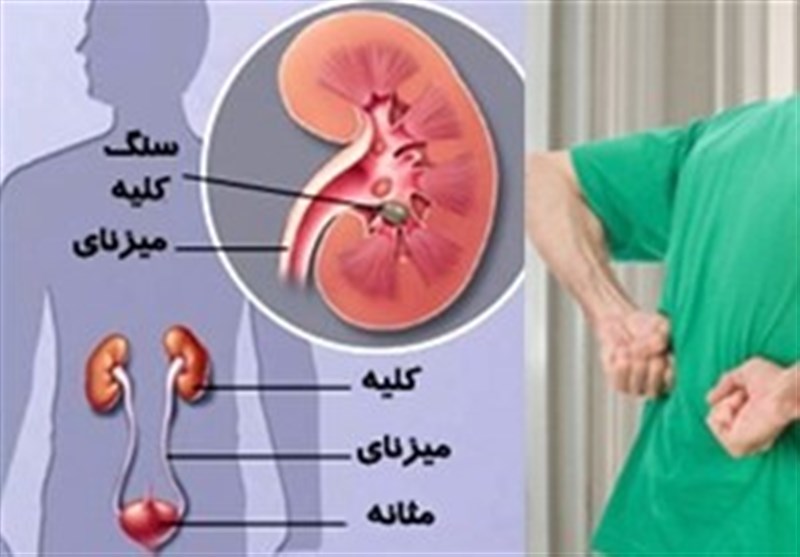

تومور سرطانی کلیه یکی از موذی ترین تومور ها هستند که در اغلب مواقع علیرغم انتشار به مناطق دیگر بدن هیچ علامت و نشانه ای ندارند و در اغلب موارد به صورت اتفاقی و در بررسی ها و چکاب کلیه با سونوگرافی و یا سی تی اسکن.

در هر ساعت کلیه های بدن انسان حدود ۷ لیتر مایع را از خون جدا می کنند این مایع را تصفیه کرده و مواد مفید و سودمند آن را به خون بازمی گردانند و مواد مضر آن را از راه میزنای به مثانه می فرستد تا دفع شوند. کجای بدنتان درد می کند مراجعه کنید آیا کلیه تان درد می کند درد کلیه در اثر عفونت کلیه یا آسیب رسیدن به آن ایجاد می شود. اما کار و وظیفه کلیه ها در بدن چیست بیا یاد بگیریم. زمانیکه کلیه ها بدرستی فعالیت کنند مواد زائد از بدن داخل ادرار ترشح می شوند همچنین کلیه ها در تنظیم سایر مواد معدنی در بدن مانند.